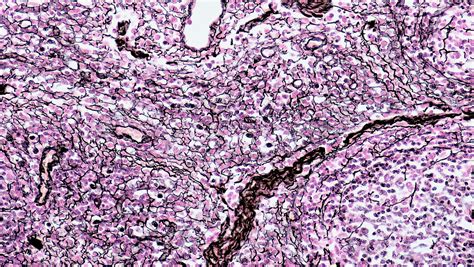

Understanding the reticular tissue location is crucial for anyone studying anatomy or physiology. Reticular tissue, also known as reticular connective tissue, is a type of loose connective tissue found throughout the body. It plays a vital role in supporting and anchoring various organs and structures. This tissue is characterized by its network of reticular fibers, which are thin and branching, providing a flexible yet strong framework.

Reticular tissue is a specialized form of connective tissue that consists of reticular fibers and reticular cells. The reticular fibers are composed of type III collagen and are produced by reticular cells. These fibers form a delicate network that supports and anchors other cells and tissues. Reticular tissue is found in various locations throughout the body, each serving specific functions.

Reticular fibers are thin, branching fibers composed of type III collagen. These fibers form a delicate network that provides structural support and flexibility. The reticular fibers are produced by reticular cells and are arranged in a mesh-like pattern, creating a scaffold that supports other cells and tissues.

Reticular cells are specialized cells that produce reticular fibers. These cells are found throughout the reticular tissue and are responsible for maintaining the tissue’s structure and function. Reticular cells also play a role in supporting the development and function of immune cells, particularly in the lymphatic system.

The ground substance is a gel-like matrix that surrounds the reticular fibers and cells. It is composed of various proteins, glycoproteins, and proteoglycans, which provide a supportive environment for the reticular tissue. The ground substance helps to maintain the tissue’s structure and function, as well as facilitating the movement of cells and molecules within the tissue.